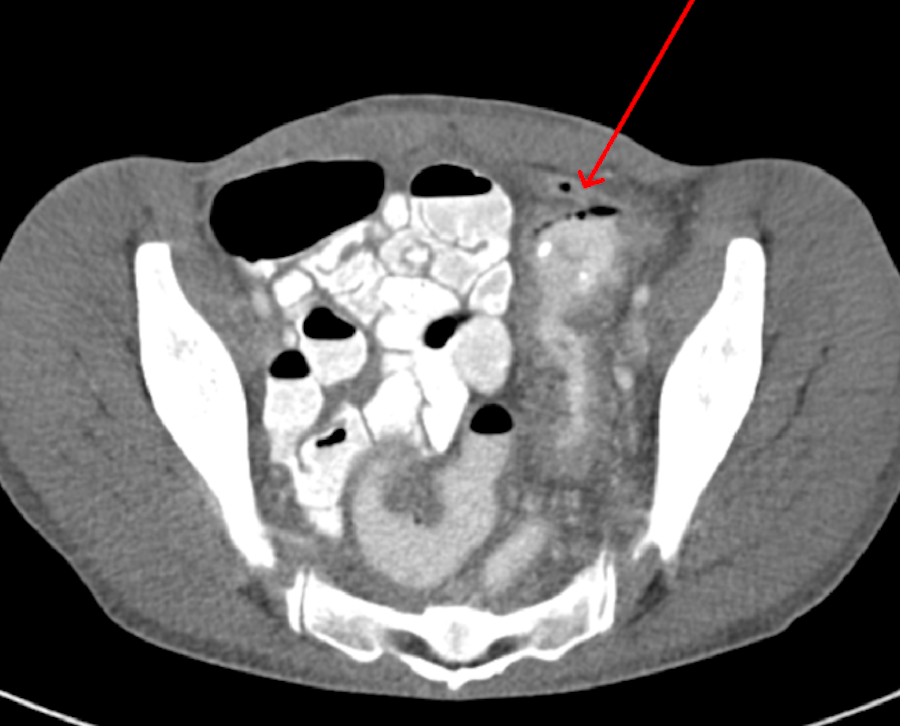

Baseline labs including complete blood count, basic metabolic panel, and liver function tests were within normal limits. Repeat CD4 count was less than 20 cells/microliter and HIV viral load was 2,76,4591 copies/mL. Erythrocyte sedimentation rate (ESR) was elevated at 60 mm/hr and stool for clostridium difficile toxin was negative. The CT scan of the abdomen and pelvis with oral and intravenous contrast re-demonstrated the thickening of the left colonic bowel wall concerning for colitis. The patient underwent cystogram which showed colovesical fistula connecting to the proximal sigmoid colon (Figure 2).